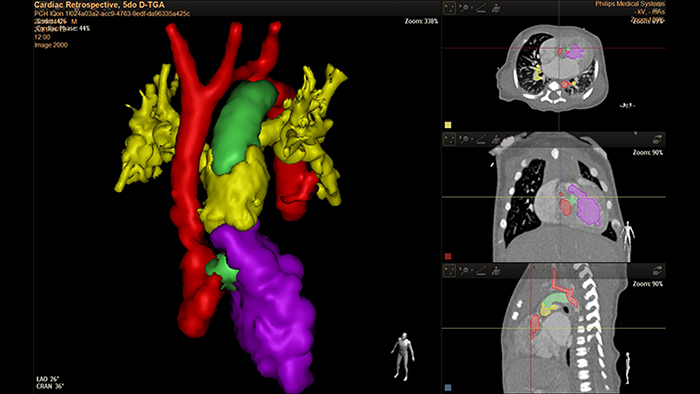

5-day old D-TGA analysis with HeartNavigator

3D modeling with IntelliSpace Portal